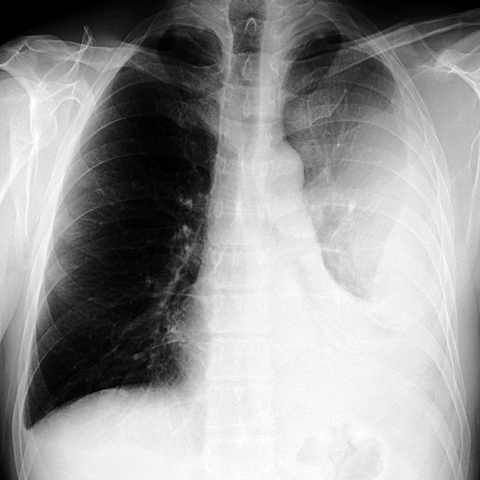

Large, Loculated Pleural Effusion [1 of 3]